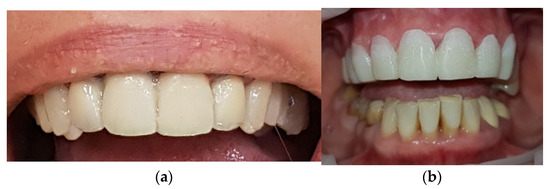

2. Case Report